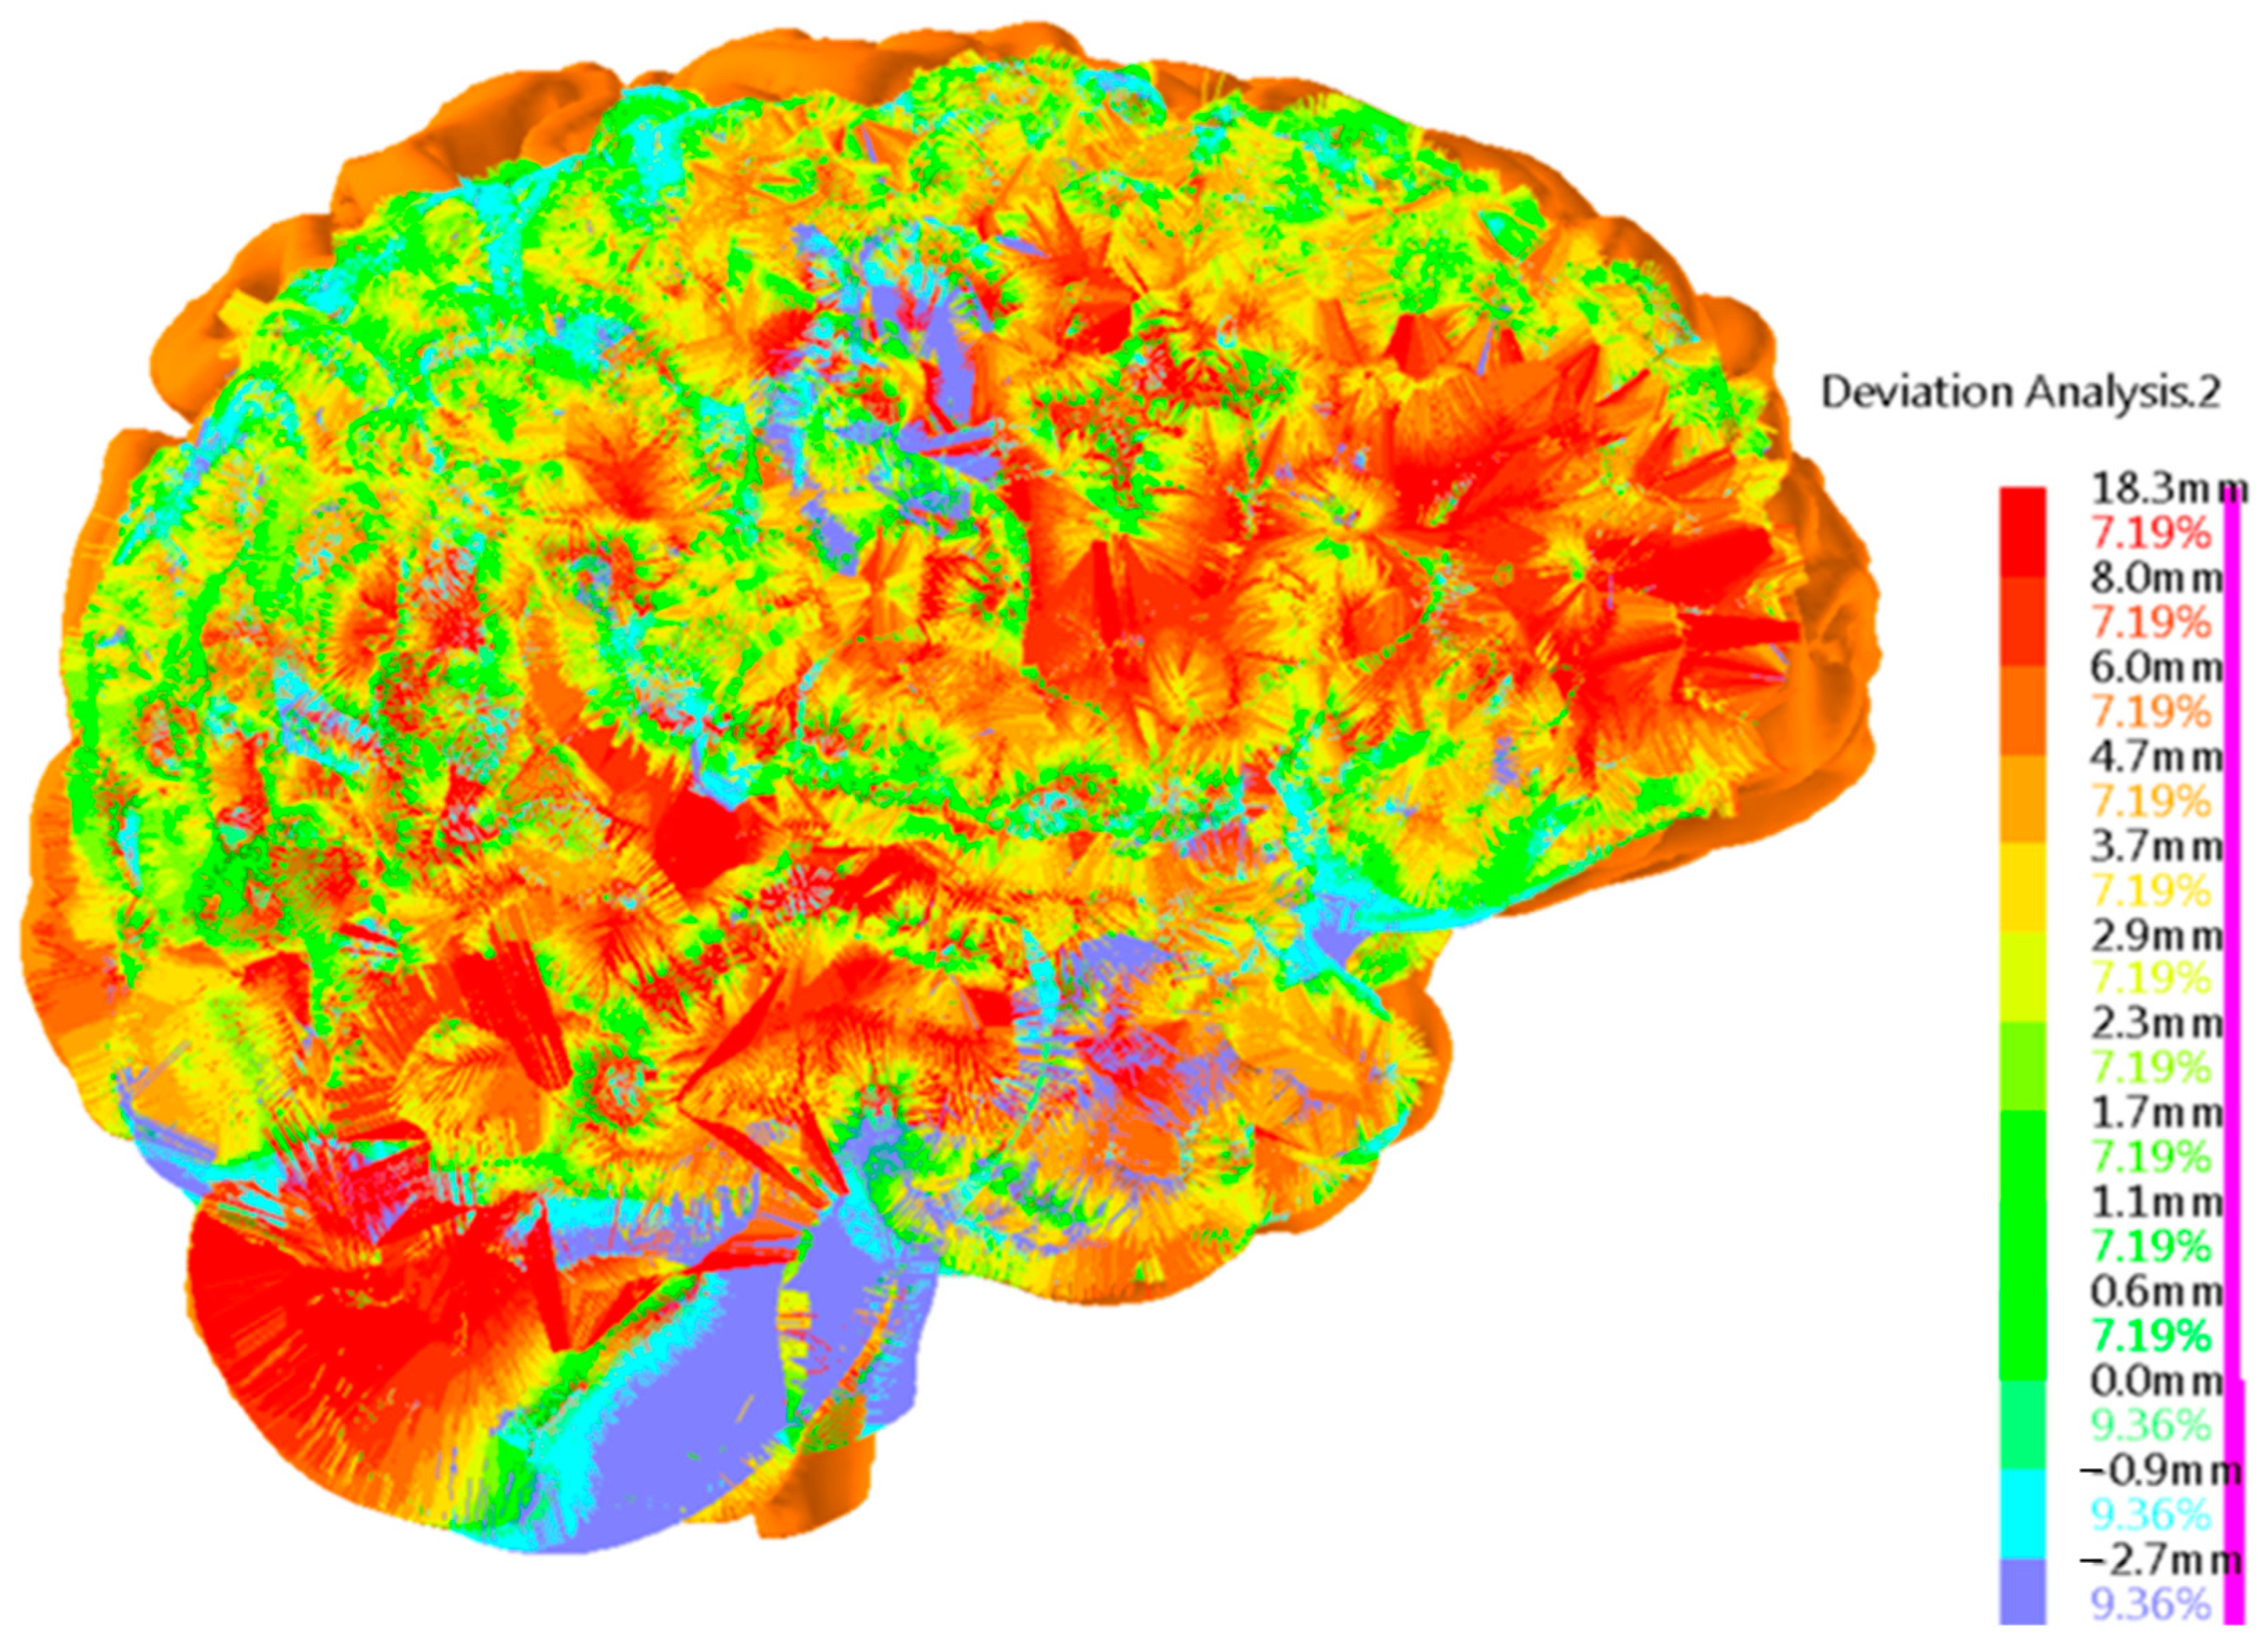

Brain Physical Differences

| Brain Parameters (White and Grey Matter) | Young Adults (28 y)  | Senior (77 y) | Difference (Young Adult vs. Senior) | Comments |

| Brain Volume | 1.0406 [dm3] | 0.98088 [dm3] | 5.7% | Young Adults: On average, young adults tend to have larger brain volumes compared to older adults, with a ~6% difference. This is largely due to ongoing brain development and growth during childhood and adolescence [40]. Senior Adults: Brain volume typically decreases with age. This reduction can be attributed to factors such as loss of neurons and their connections, as well as changes in brain structural integrity. This decrease in volume can affect various cognitive functions. |

| Brain Area | 165,893.3 [mm3] | 1,619,62.1 [mm2] | 2.4% | Young Adults: Younger individuals generally have a larger brain area compared to older adults, with a ~2% difference. The brain area encompasses the surface of the brain, which is important for processing information and facilitating communication between different brain regions. Senior Adults: Over time, there may be a slight reduction in the brain’s surface area. This could be related to the gradual decline in cognitive functions, such as memory and processing speed, experienced by some older individuals. |

| Brain Mass | 1.18 [kg] | 1.02 [kg] | 13.3% | Young Adults: Young adults typically have greater brain mass compared to older adults, with a ~13% difference. Brain mass is closely related to brain volume and is largely responsible for the organ’s overall functionality. Senior Adults: As individuals age, there is often a decline in brain mass, primarily due to a decrease in the number of neurons and synaptic connections. This mass reduction can contribute to age-related cognitive decline. |